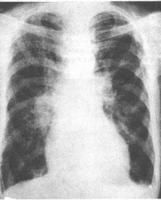

除與有關相應的的發病徵象外,當肺剛受損的數小時內,患者可無呼吸系統症狀。隨後呼吸頻率加快,氣促逐漸加重,肺部體徵無異常發現,或可聽到吸氣時細小濕囉音。X線胸片顯示清晰肺野,或僅有肺紋理增多模糊,提示血管周圍液體聚集。動脈血氣分析示Pao2和PaCO2偏低。隨著病情進展,患者呼吸窘迫,感胸部緊束,吸氣費力、紫紺,常伴有煩躁、焦慮不安,兩肺廣泛間質浸潤,可伴奇靜脈擴張,胸膜反應或有少量積液。由於明顯低氧血症引起過度通氣,PaCO2降低,出現呼吸性鹼中毒。呼吸窘迫不能用通常的氧療使之改善。如上述病情繼續惡化,呼吸窘迫和紫紺繼續加重,胸片示肺部浸潤陰曩大片融合,乃至發展成“白肺”。呼吸肌疲勞導致通氣不足,二氧化碳瀦留,產生混和性酸中毒。心臟停搏。部分患者出現多器官衰竭。

X線胸片肺功能測定

4、胸部X線檢查顯示兩肺浸潤陰影。